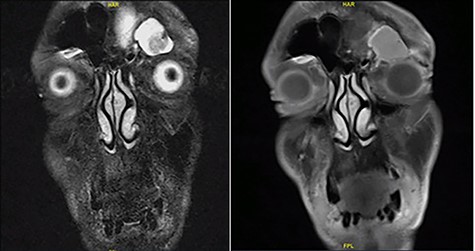

The left eyelid swelling was causing inferior globe dystopia with mild tenderness on palpation, but no redness, fluctuation or cutaneous changes (Fig. 1). The extraocular muscle movements were intact, except for limited left supraduction due to the eyelid swelling. The pupils were equal and reactive, and visual acuity and color vision were normal. Transnasal endoscopic examination was unremarkable bilaterally. Contrasted sinus computed tomography (CT) scan showed an expanding left frontal sinus hyperdense opacification with peripheral enhancement and extension to the left orbit (Fig. 2). Magnetic resonance imaging (MRI) showed a loculated mucocele in the left frontal sinus with hypertense T1 signal and extension to left orbit but no intracranial extension (Fig. 3).

Face MRI showing a mass in the left frontal sinus with hypertense T1 signal and extension to left orbit.